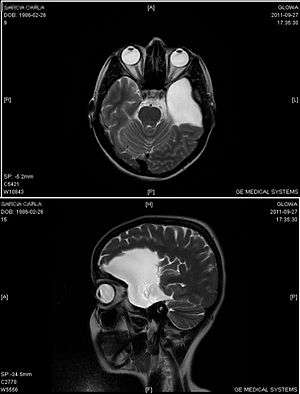

An MRI of a 25-year-old woman with left frontotemporal arachnoid cyst. | |

Diagnosis is principally by MRI. Frequently, arachnoid cysts are incidental findings on MRI scans performed for other clinical reasons. In practice, diagnosis of symptomatic arachnoid cysts requires symptoms to be present, and many with the disorder never develop symptoms.